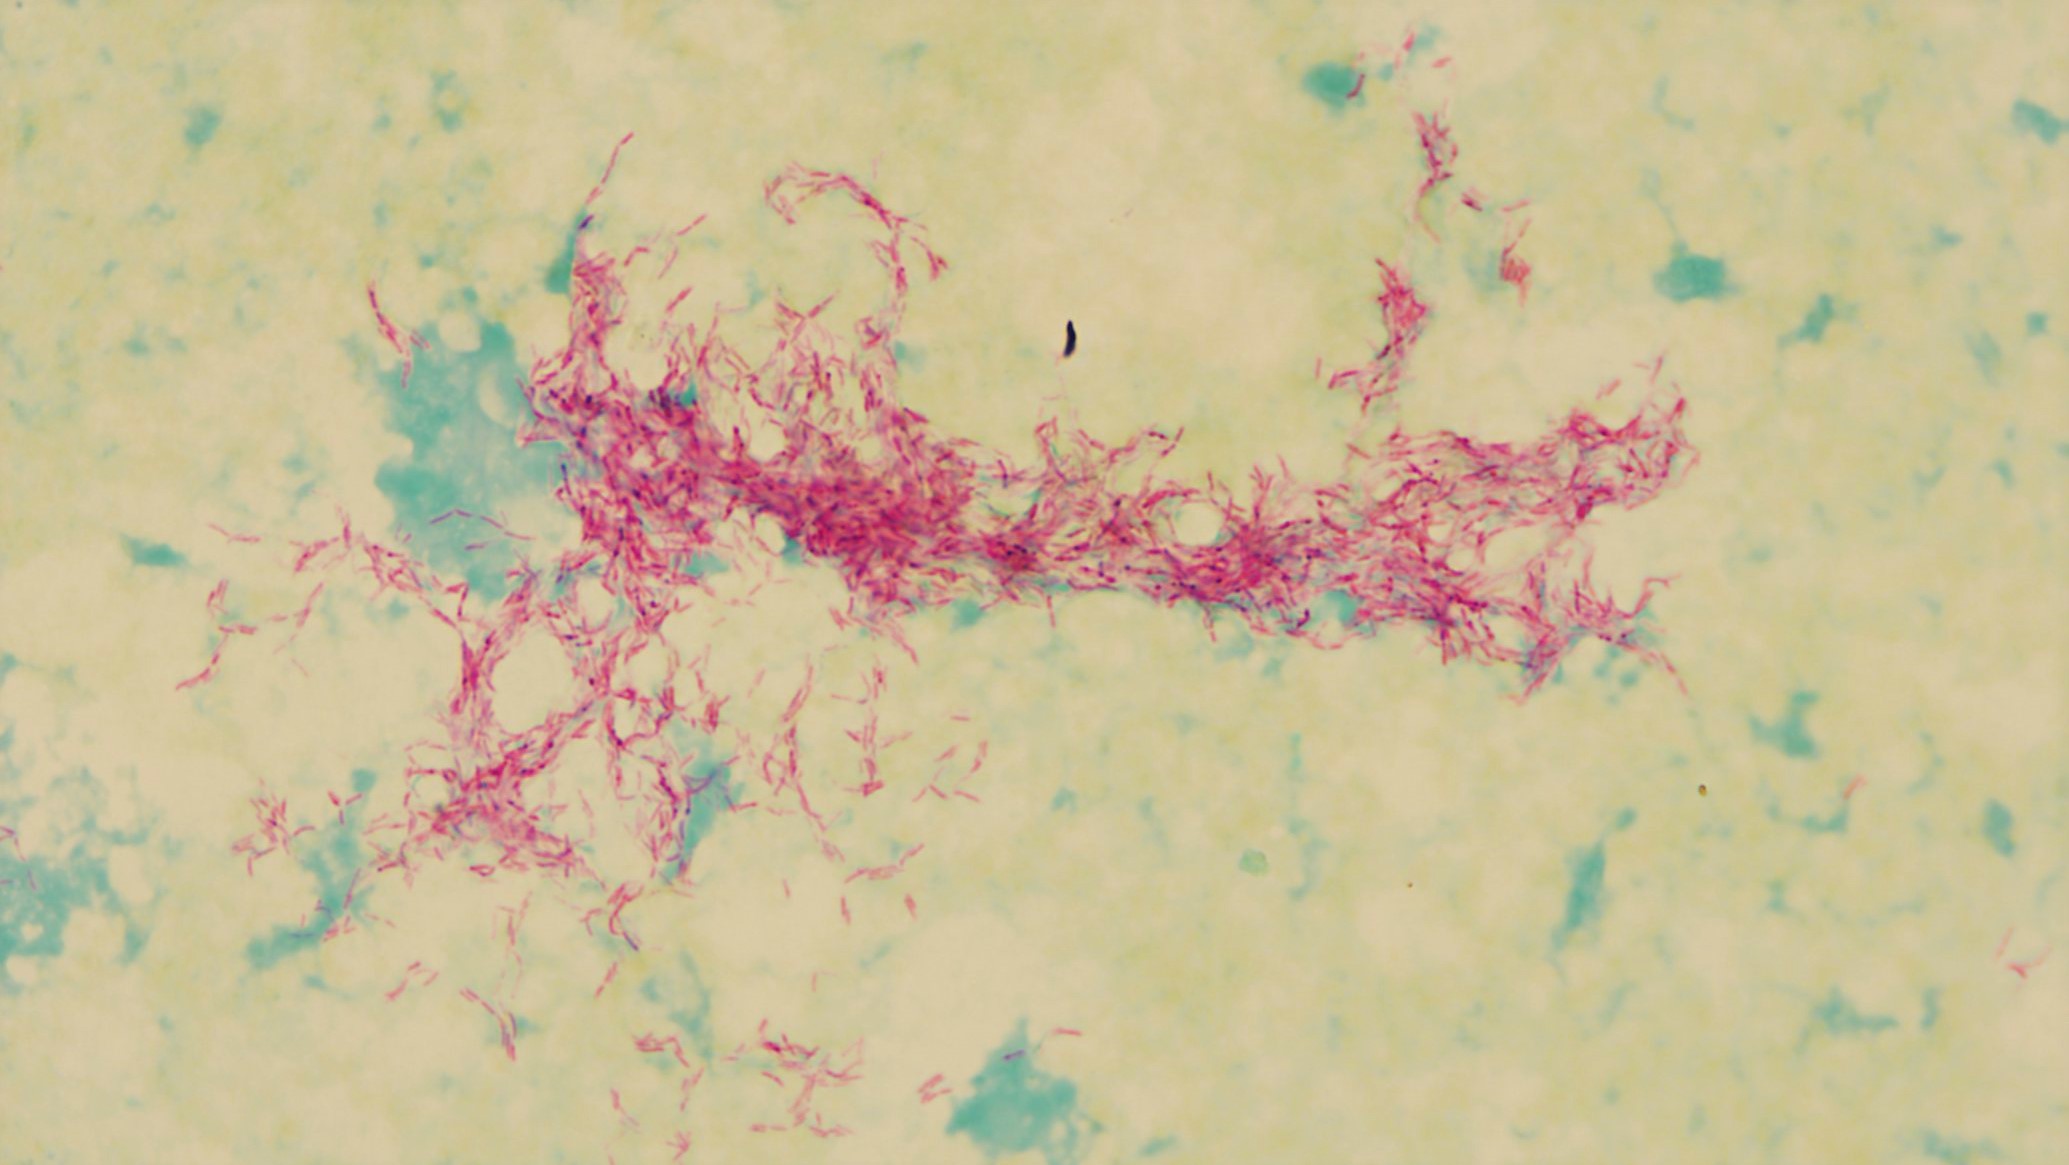

結核菌( M. tuberculosis ) は、ヒトに結核 (TB)を引き起こす細菌です。結核は主に肺に影響を及ぼす病気ですが、体の他の部分にも影響を与える可能性があります。これは、風邪やインフルエンザと同じように、感染性結核患者から放出される空気中の飛沫を介して広がります。

- 喀痰培養。喀痰とは、肺から吐き出される粘液と唾液の標本です。